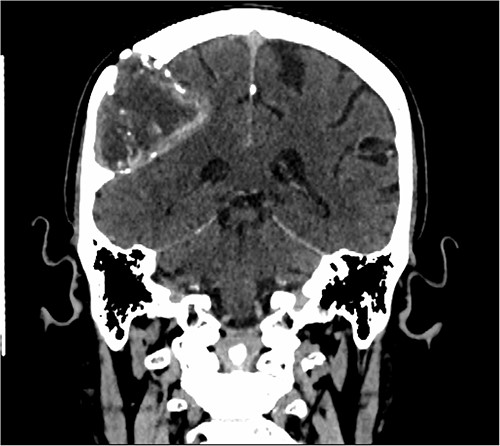

Our patient is a 76-year-old gentleman with medical history of hypertension and lumbar spondylosis. He did not have any previous history of trauma or systemic infections. He had presented to his local hospital with a 2-day history of left arm numbness. He did not report any headaches or giddiness. On clinical assessment, he did not have any neurological deficits. A CT brain and MRI brain (Figs 1–5) with contrast revealed a 53 × 53 × 41 mm partially calcified, heterogeneously enhancing conical shaped right extra-axial parietal convexity lesion. The overlying calvarial bone was remodelled and possibly eroded. There was evidence of prior haemorrhage within the lesion and scattered internal and peripheral calcification. Based on these characteristics, the possible diagnoses were that of an intraosseous meningioma, haemangioma and giant cell tumour. Patient was consented for craniotomy and excision of the tumour.

Axial CT scan showing the extra-axial lesion with surrounding bone remodelling.